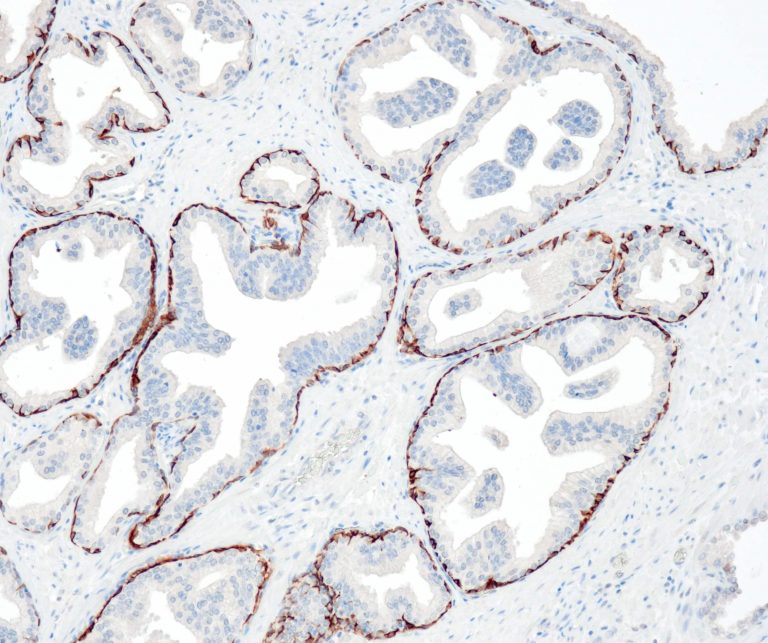

Breast Pathology